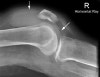

- Small

This patient presented with a history of dislocated right patella.

There is a small amount of fluid in the supra- patella pouch (left arrow) and in Hoffa's Triangle (right arrow).